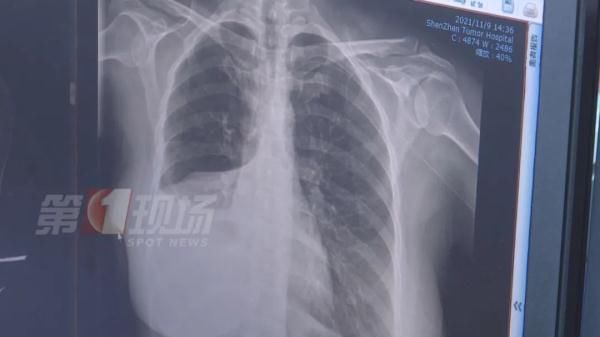

文章插图

江女士做了增强CT后,确实发现肺部有一个五公分左右的肿瘤,医生诊断为肺癌,目前为中期偏早,建议她进行切除手术。